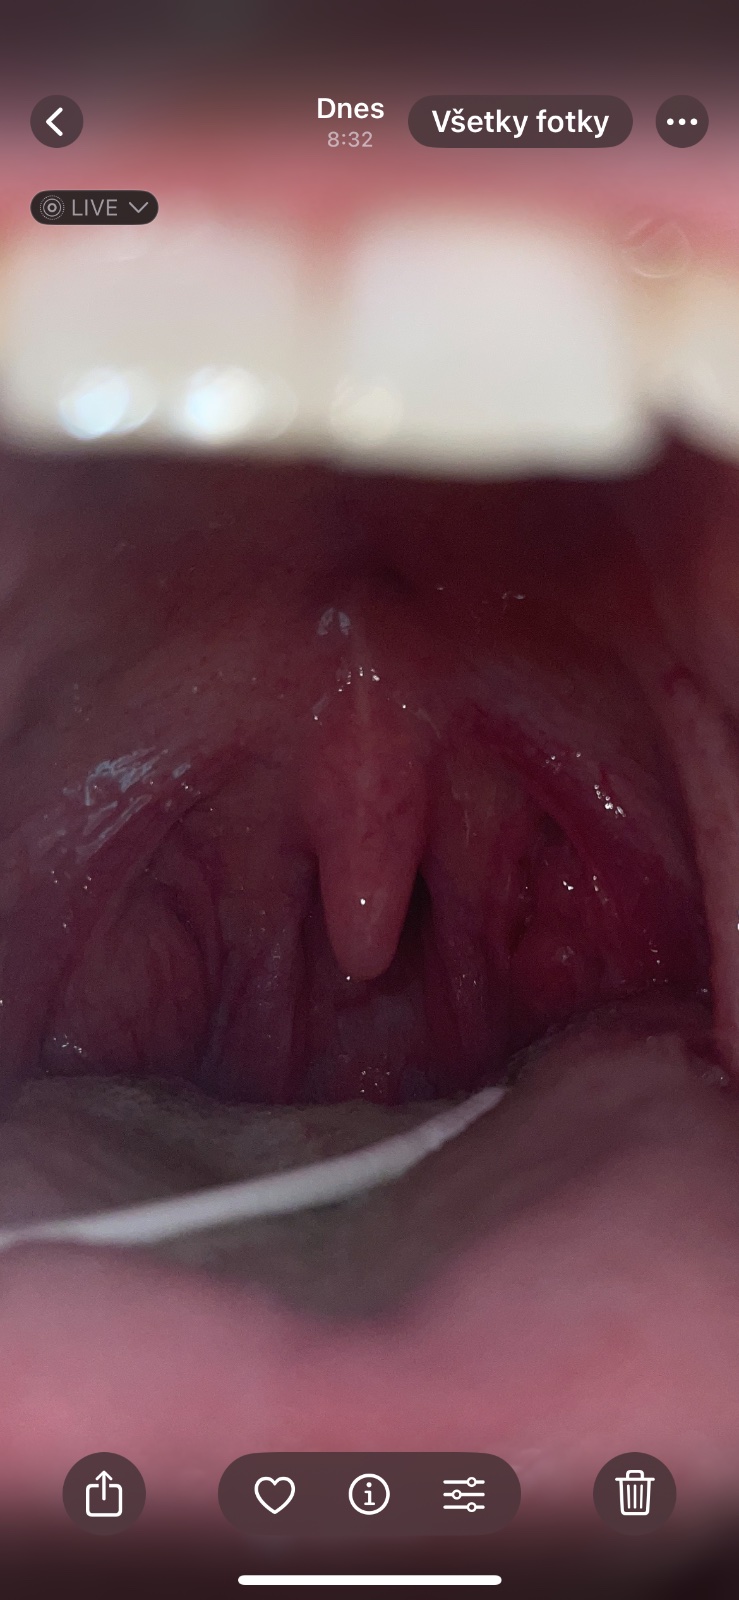

Ja mám dlhodobejšie problém že si vytlacam biele bodky odtial, jednu mám peknu a druhu mám takú zvláštnu , vijde mi to z hoci kade (taka deravá) a teda aj keď si len prechádzam tycinkou vatovou po nej zapácha.

Na orl som bola , lekárka povedala že nieje to take strašne , ale že nech sa sama rozhodnem či ísť vybrať či nie…